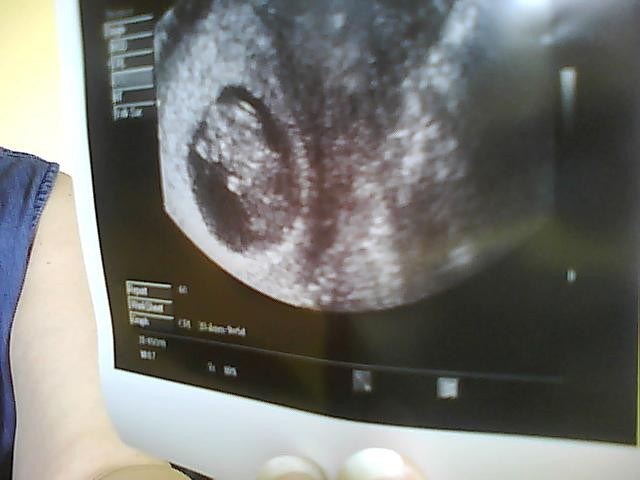

Ja igen har jeg haft lidt travlt med familien siden fredag, så har ikke været online! Men.. Fredag 9+5 var jeg til scanning og så det fineste lille menneske, der er vokset helt som det skal, med et hjerte der hamrede derudaf og en fostersæk der er blevet så flot og rund !!! .. Piger nu kan jeg virkelig ikke se noget skulle kunne gå galt...

Det er bare så Urealistisk! I får lige et billede af min lille guldklump!

Vedhæftede fotos (klik for at se i fuld størrelse)